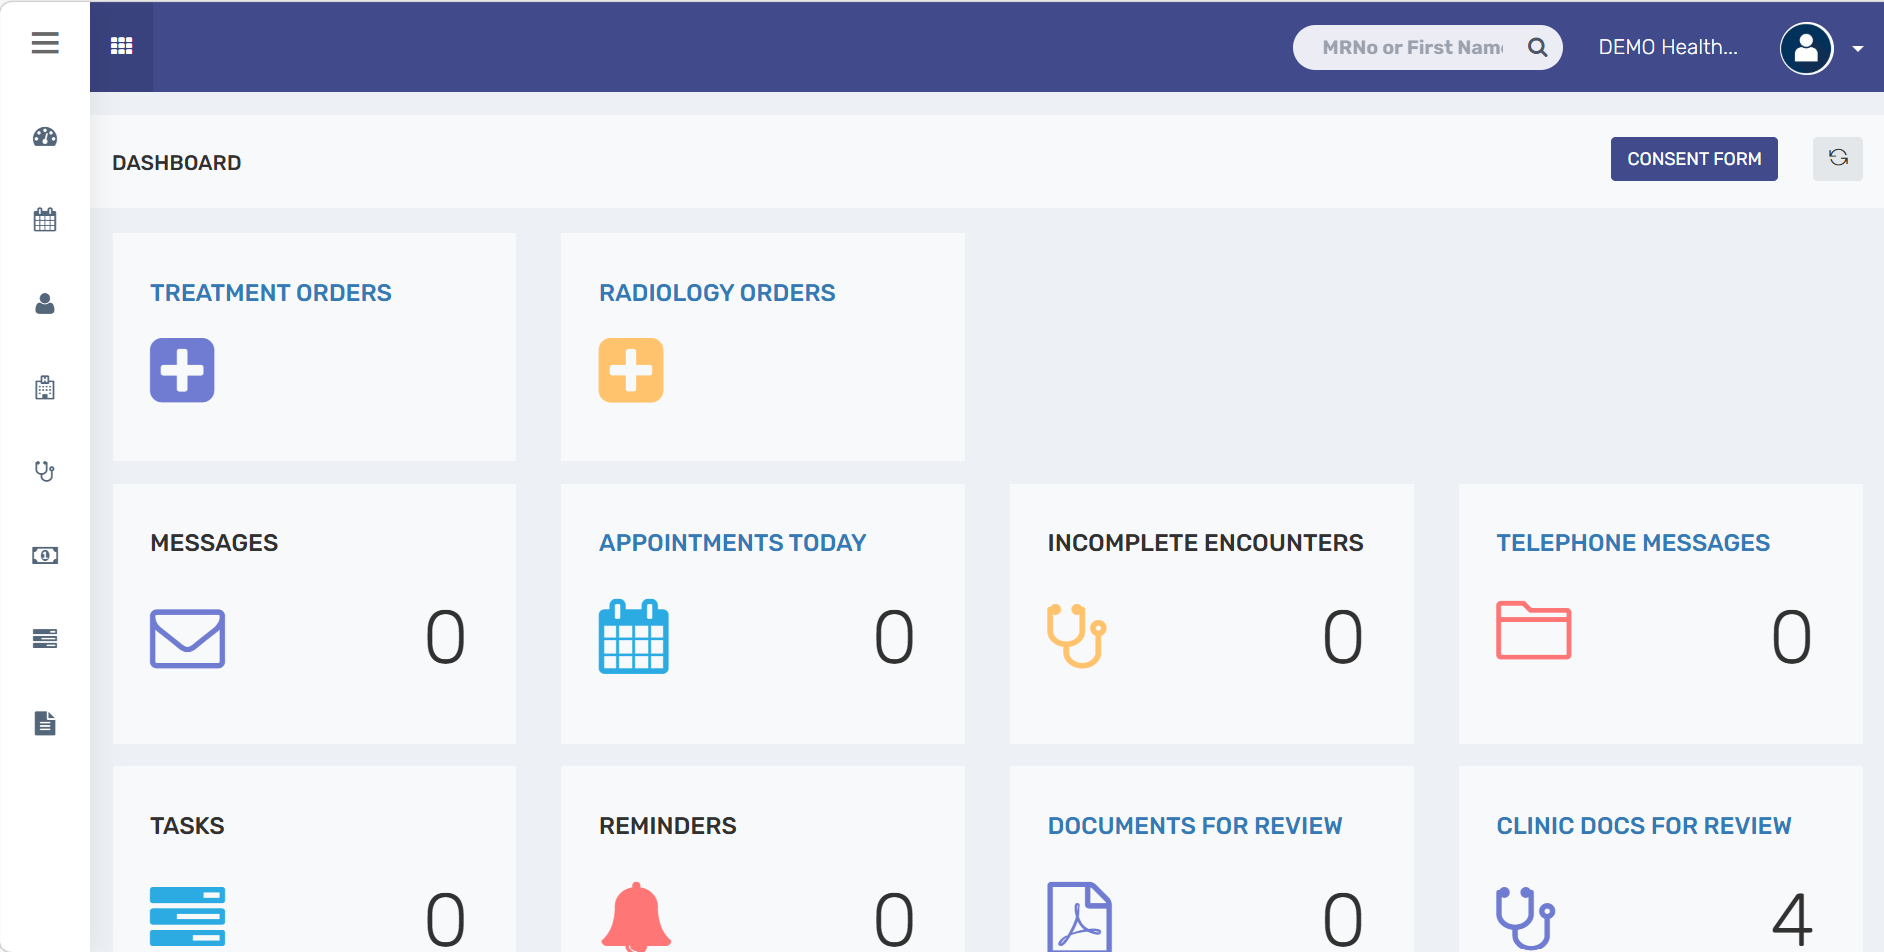

One platform to manage your complete EMR workflow

Built for modern healthcare—secure, reliable, and

ready for ADHICS, Shafafiya, Malaffi, and NABIDH.

A unified EMR platform for clinics and homecare providers to manage patient records, appointments, billing, care plans, and daily operations with ease.

Clinics/School Clinics

-

Registration

-

Appointments

-

Electronic Medical Records

-

Physician Note, Nursing Note

-

Clinical Coding

-

eClaim Management

-

ADHICS Compliance, Malaffi & NABIDH Integration

Everything you need

manage care, compliance, and clinical workflows

More than software—it is a complete, implementation-ready EMR platform for modern healthcare providers